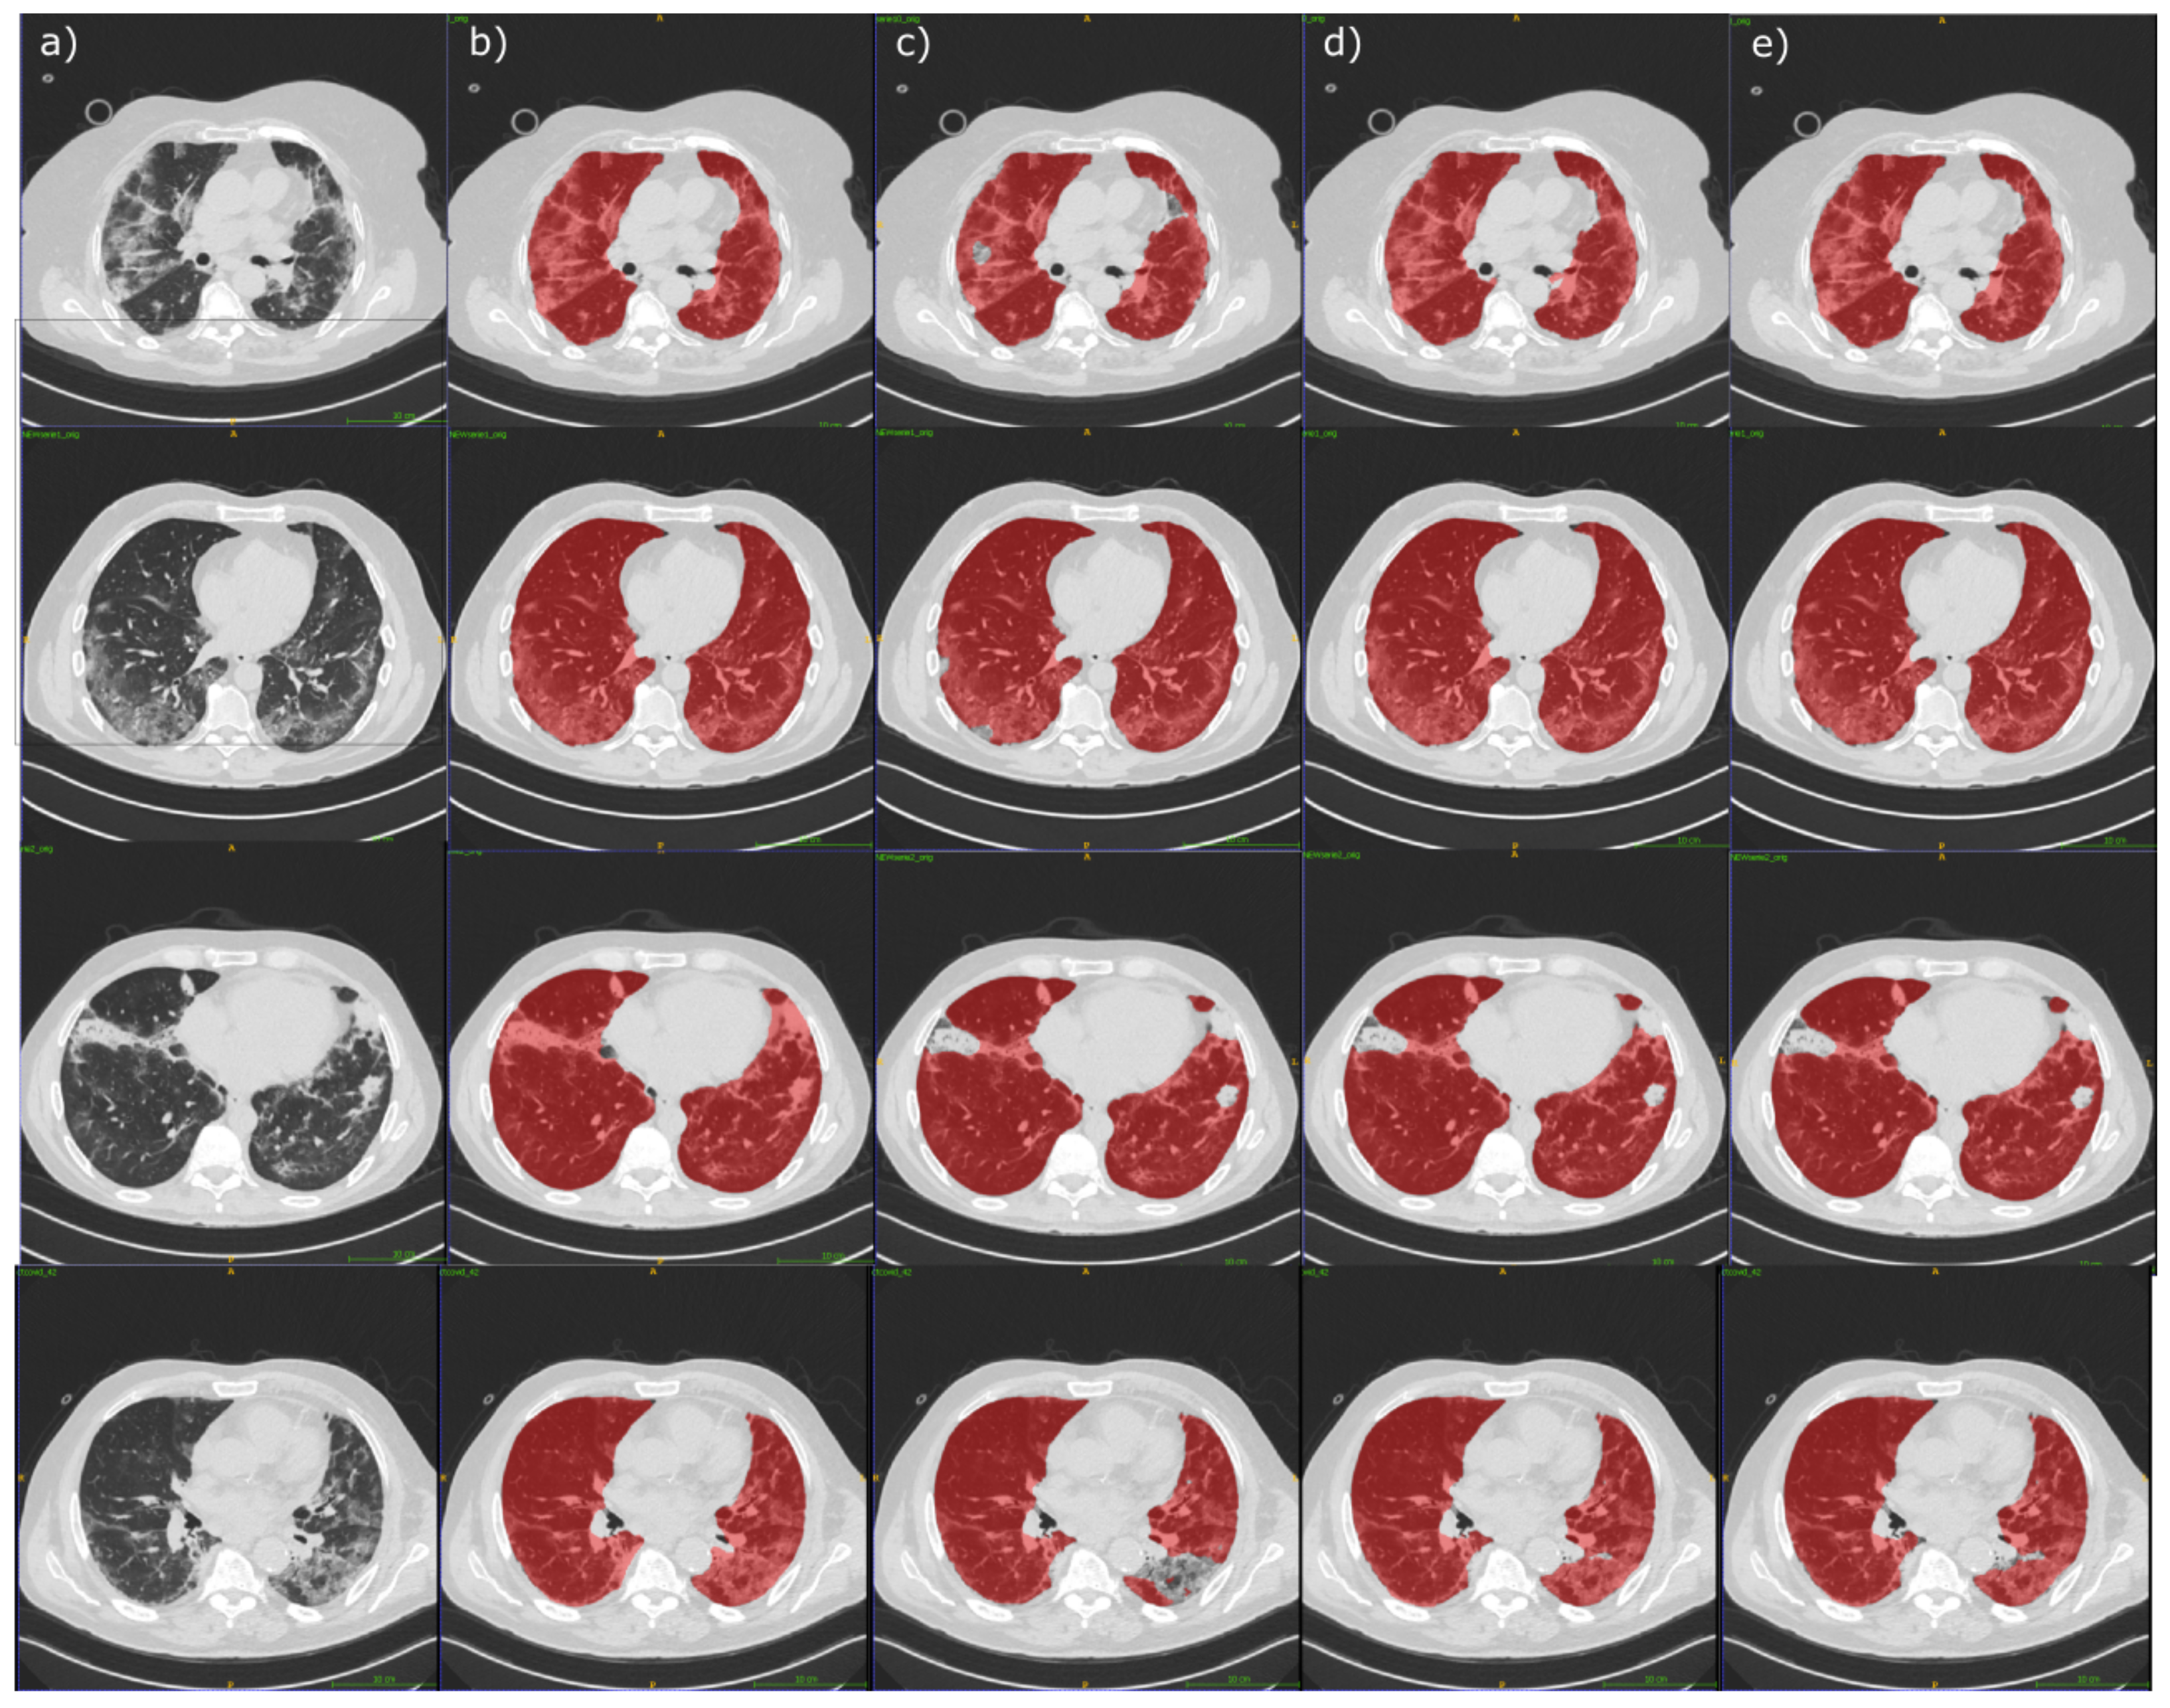

4.2. Segmentation Experimental Results